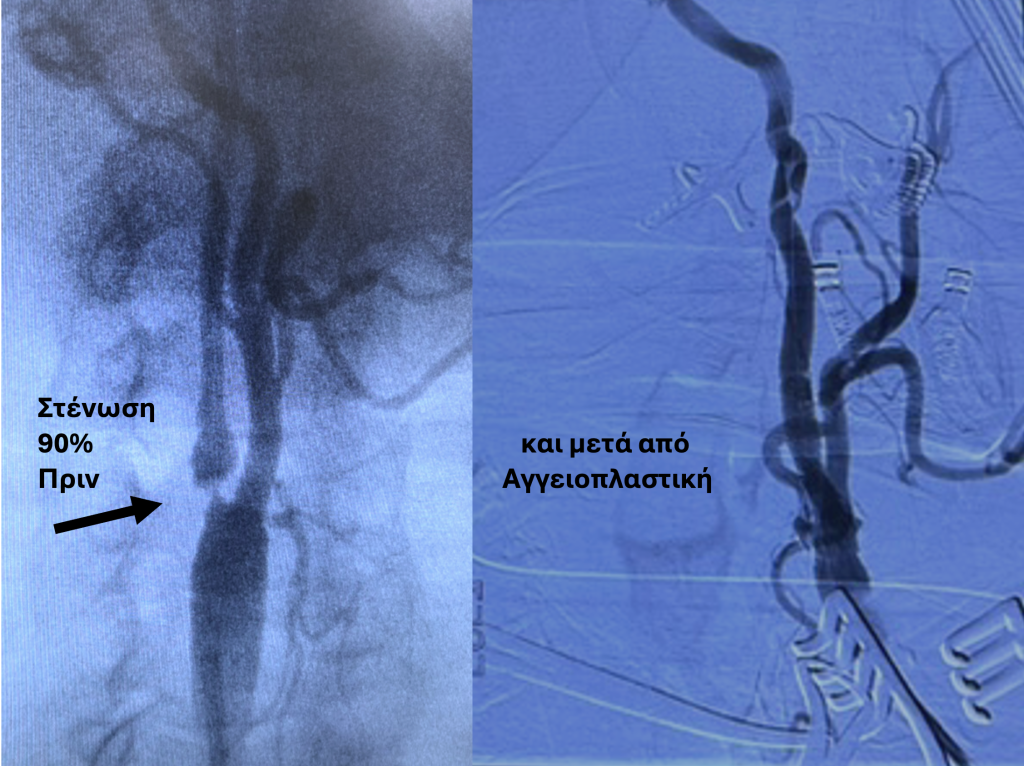

- Ενδαγγειακή θεραπεία με τοποθέτηση stent – Αγγειοπλαστική. Με τοπική αναισθησία και παρακέντηση της μηριαίας, γίνεται διάνοιξη της στένωσης με ειδικό μεταλλικό πλέγμα (stent) και μπαλονάκι, αποκαθιστώντας τη ροή του αίματος.